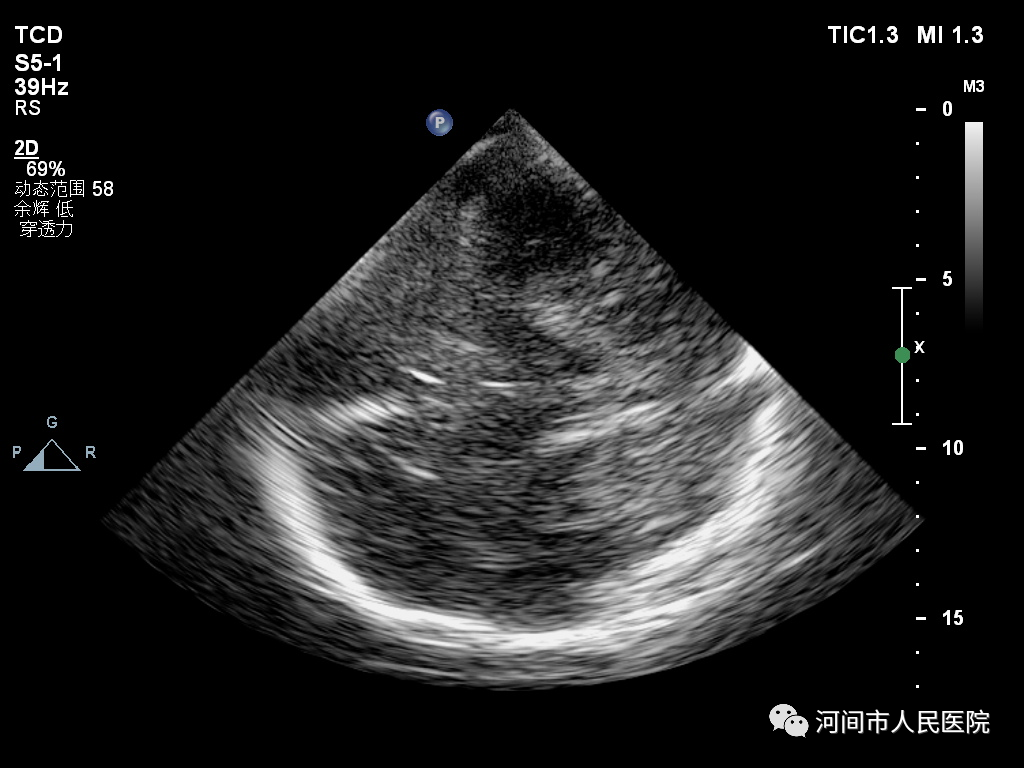

患者取仰臥位,檢查者將探頭緊貼於(yu) 患者顱骨兩(liang) 側(ce) 顳窗進行檢查。

正常的中腦黑質類似一隻黑色的蝴蝶,其內(nei) 部回聲呈均質的低回聲。

I級:呈均勻分布的低回聲;Ⅱ級:見散在點狀、細線狀稍強回聲;Ⅲ級:回聲呈斑片狀增強,低於(yu) 腳間池回聲;Ⅳ級:回聲呈斑片狀增強,等於(yu) 腳間池回聲;V級:回聲呈斑片狀增強,高於(yu) 腳間池回聲。